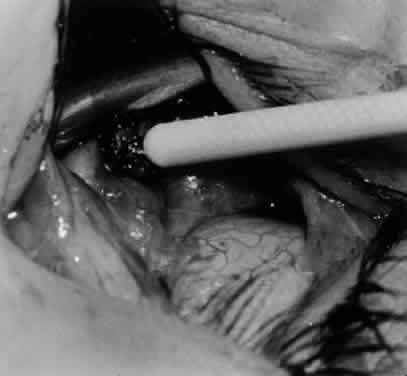

Fig. 26. Cautery is applied to sever the neurovascular bundle, and a sponge is used to protect the sclera and lids from cautery.

Fig. 27. As the neurovascular bundle is severed completely, the inferior oblique muscle will be released of the normal tension provided by the neurovascular bundle on the posterior border of the inferior oblique muscle.